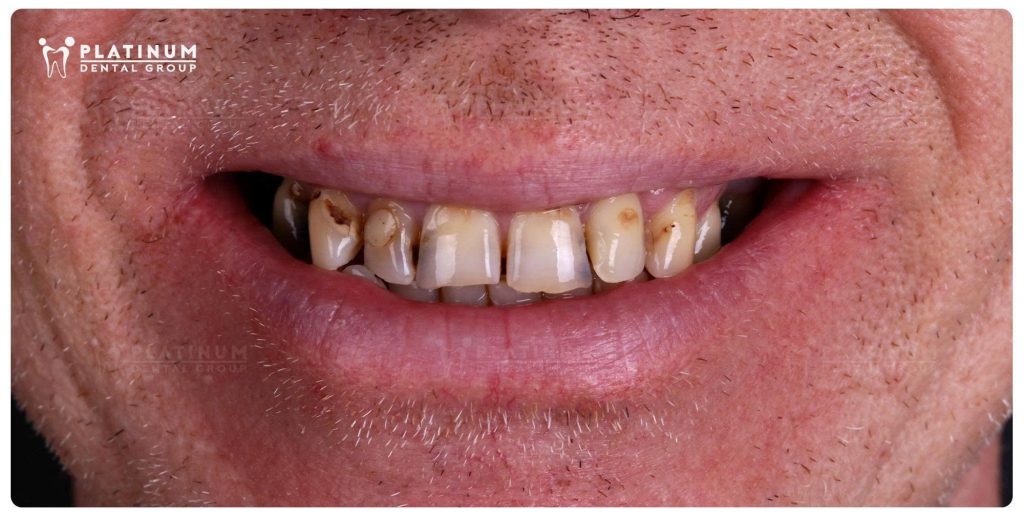

Tình trạng mất răng hàm kéo dài, cùng với các răng còn lại bị sâu và vỡ mẻ, không chỉ ảnh hưởng đến thẩm mỹ mà còn làm suy giảm nghiêm trọng chức năng ăn nhai. Những bữa ăn yêu thích dần trở nên không còn trọn vẹn, và sự tự tin trong giao tiếp cũng theo đó mà thu lại.

Kết quả sau điều trị không chỉ thể hiện ở sự thay đổi về thẩm mỹ. Đó còn là cảm giác ăn nhai ổn định hơn, thoải mái hơn trong sinh hoạt hằng ngày. Là sự tự tin khi giao tiếp trở lại. Và là khoảnh khắc Mr. Jeffrey xúc động khi nhìn thấy chính mình trong gương với nụ cười mới.